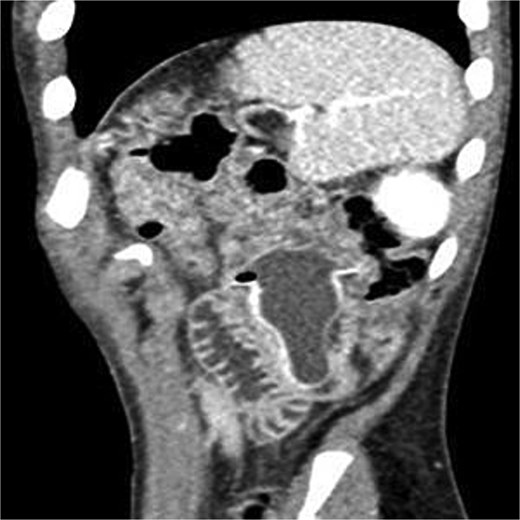

CT abdomen with contrast: Foreign body in the proximal jejunum with partial obstruction, dilated appendix (9 mm) with wall enhancement and fat stranding consistent with acute appendicitis (Fig. 1).

CT sagittal view showing fluid-filled nipple of feeding bottle lodged in jejunum.